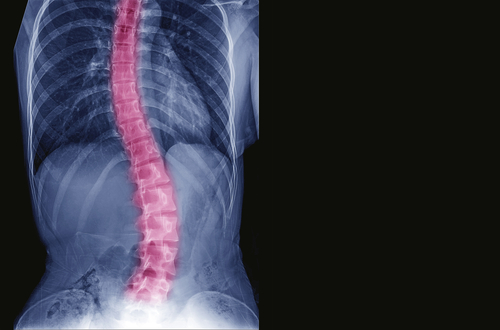

- Scoliosis

The simplest answer to this question is, yes. It is definitely possible for a chiropractor to fix noticeable body posture problems like a higher left shoulder that has occurred with time. Postural deformities like this can be very serious and can be very harmful to the spine and nervous system. In this case, visiting the chiropractor can be effective.

There are numerous postural problems, here are a few postural problems that can be cured by a chiropractor.